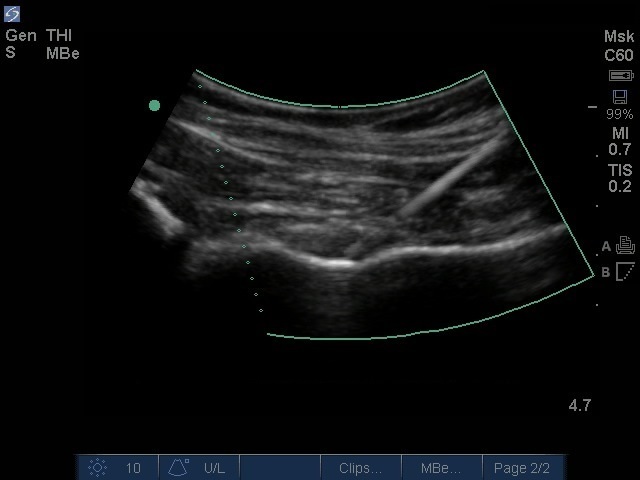

曲線針強化技術と臀部注射の画像